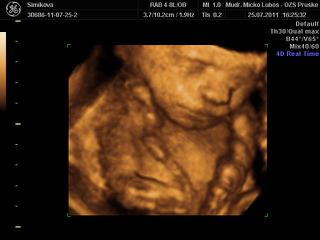

dnes som sa objednala na 3D do hlohovca, som strasne zvedava a nedockava co cakame, hned mi dali termin 9cakala som , ze budem 3tyz cakat), ale ideme uz vo stvrtok. Som zvedava, niako niesom nadcena 3Dckami, sa mi foto deticiek nepaci, take stlacene kadejake.... ani s malym som nebola, ale u neho som vedela, ze chlapec to bude, no tento pocit, ze neviem ma nici, nic si nemozem chystat 😝